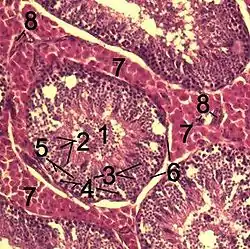

![]() Histological section through testicular parenchyma of a boar. 1 Lumen of convoluted part of the seminiferous tubules, 2 spermatids, 3 spermatocytes, 4 spermatogonia, 5 Sertoli cell, 6 myofibroblasts, 7 Leydig cells, 8 capillaries | |

Leydig cells, also known as interstitial cells of the testes and interstitial cells of Leydig, are found adjacent to the seminiferous tubules in the testicle and produce testosterone in the presence of luteinizing hormone (LH).[1][2] They are polyhedral in shape and have a large, prominent nucleus, an eosinophilic cytoplasm, and numerous lipid-filled vesicles.[3]